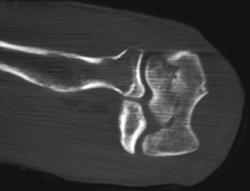

Calcaneal Fracture